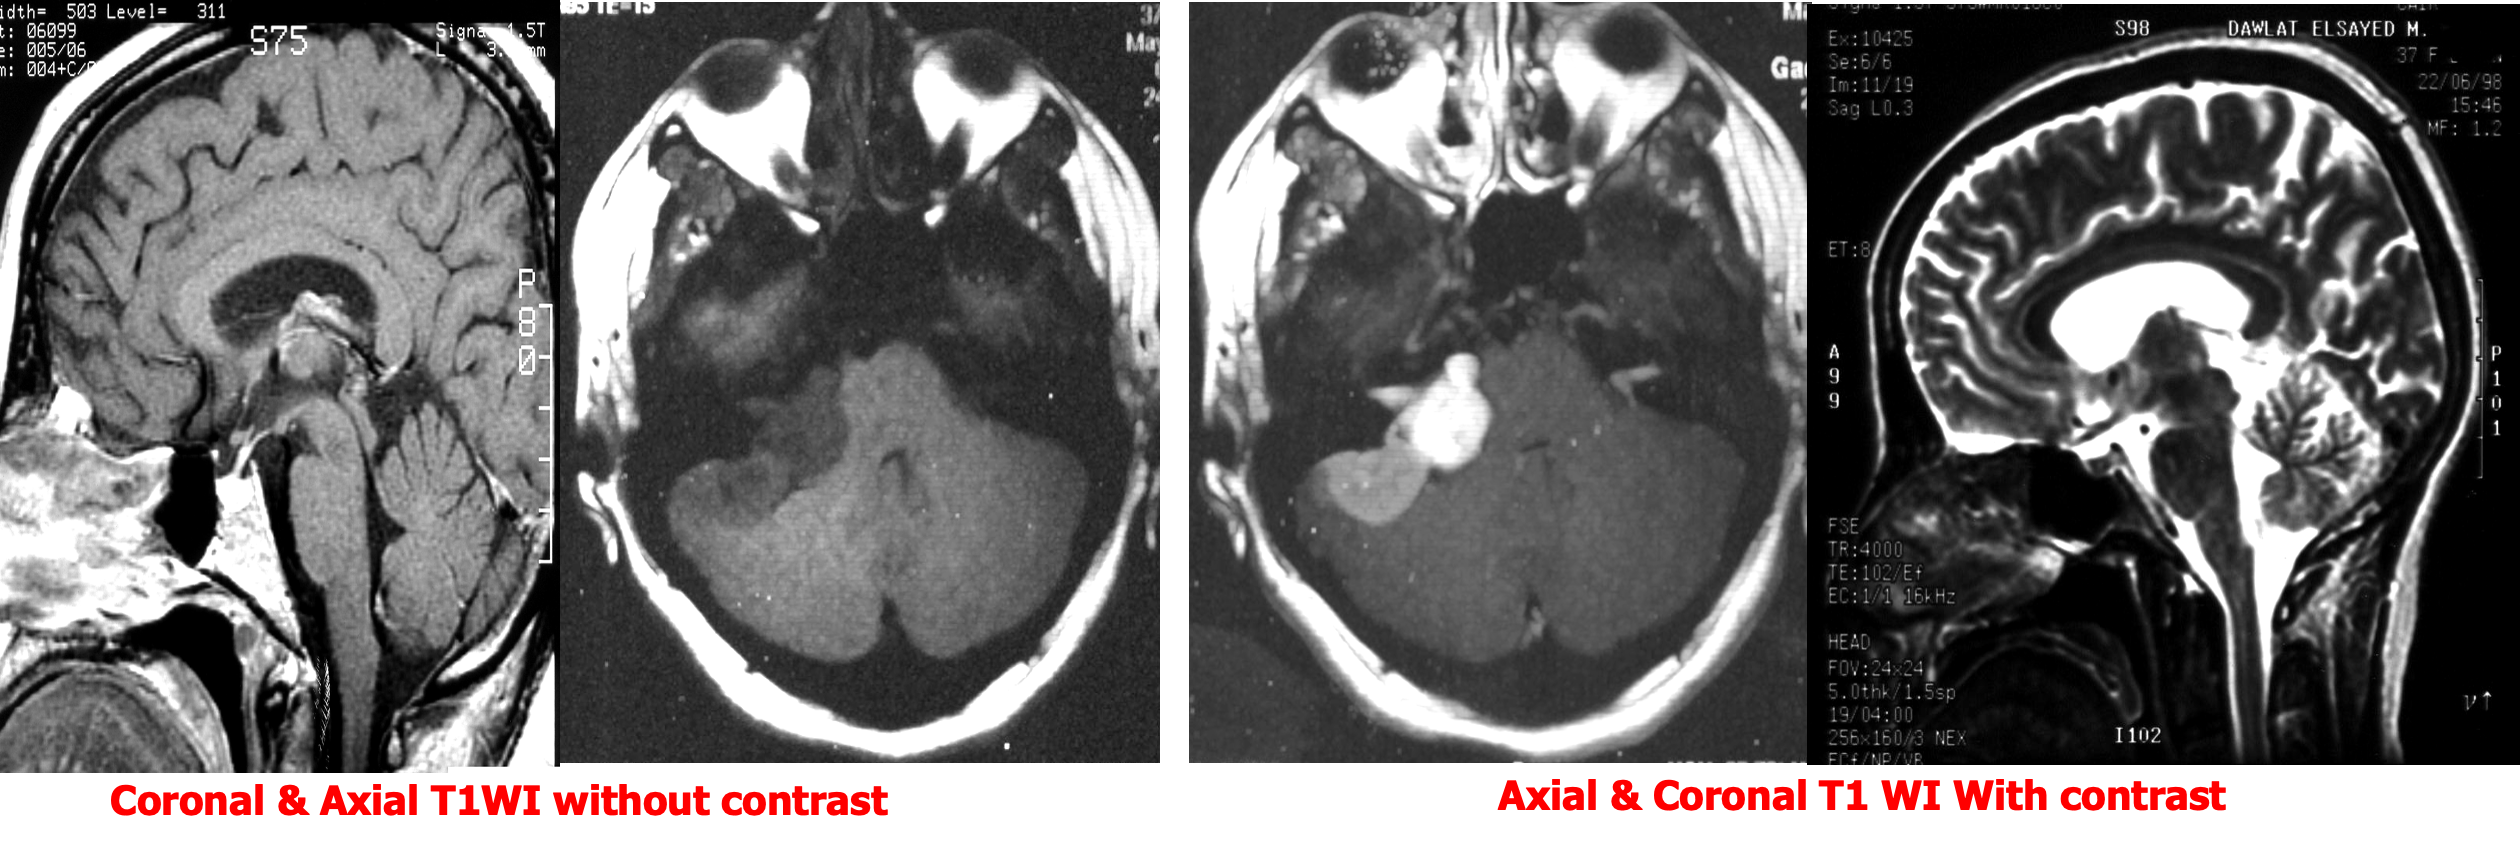

Gadolinium – DTPA

Only T1 weighted images are obtained after Gd- DTPA injection

- Differentiate SOLs

- Assess activity of some lesions like MS

- Assess post operative tumor recurrence